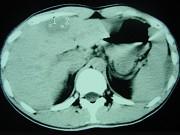

问题 男,35岁,病人低热、消瘦、乏力,左右季肋区疼痛,CT扫描如图,请选择最佳诊断()

选项 A.肝脓肿、腹腔脓肿 B.肝结核、腹腔结核 C.肝癌、腹腔转移 D.肝脏及腹腔转移瘤 E.肝海绵状血管瘤、腹腔脓肿

答案 B